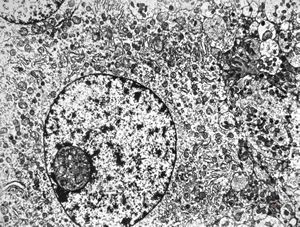

M,47y. | chromophobic pituitary adenoma